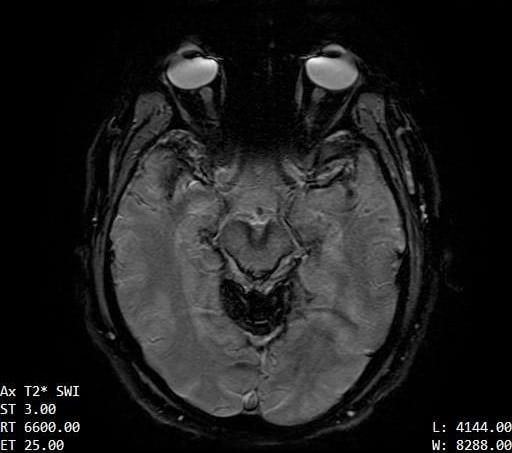

The contours of the cerebrum, cerebellum, and brainstem are outlined with a T2 hypointense signal with blooming on susceptibility weighted sequences, which is compatible with the clinical history of superficial siderosis. A majority of the T2 hypointense signal is present in the superior folia of the cerebellum but also seen coating the surfaces of the brainstem, the cortical surfaces along the Sylvian fissures, and the cortical surfaces of the paramedian sulci of the frontal and occipital lobes. Few subcortical and periventricular T2/FLAIR hyperintensities are present in both cerebral hemispheres.²

If you look at each image, you can see the dark areas where his hemosiderin deposits are. The radiologist will use the same machine and settings, so we should visually compare the new images with these for some positive change.³